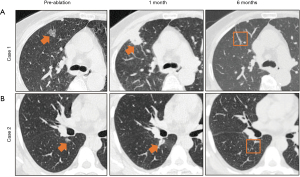

Improved LA was safe and effective in the treatment of lung adenocarcinoma manifesting as GGNs

A total of six patients (two men and four women) with eight GGNs underwent improved LA treatment. The mean age of the patients was 62.8 (range, 53 to 76) years. All the GGNs were pathologically diagnosed as lung adenocarcinoma by pre-ablation biopsy. The baseline characteristics of the patients are shown in Table 1. Contrast-enhanced chest CT is the standard method of evaluating technique efficacy at 1 and 6 months post-ablation. Representative CT images of the three GGNs before and after ablation are displayed in Figure 4. There were no ablation-related deaths in all patients. As for complications, only one patient experienced mild pneumothorax, and no cases of hemothorax and infection were observed.